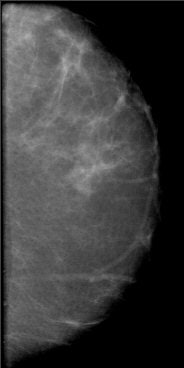

![]() |

| A 2D mammogram generated from a tomosynthesis reconstruction using advanced iterative reconstruction. Image courtesy of Dexela. |